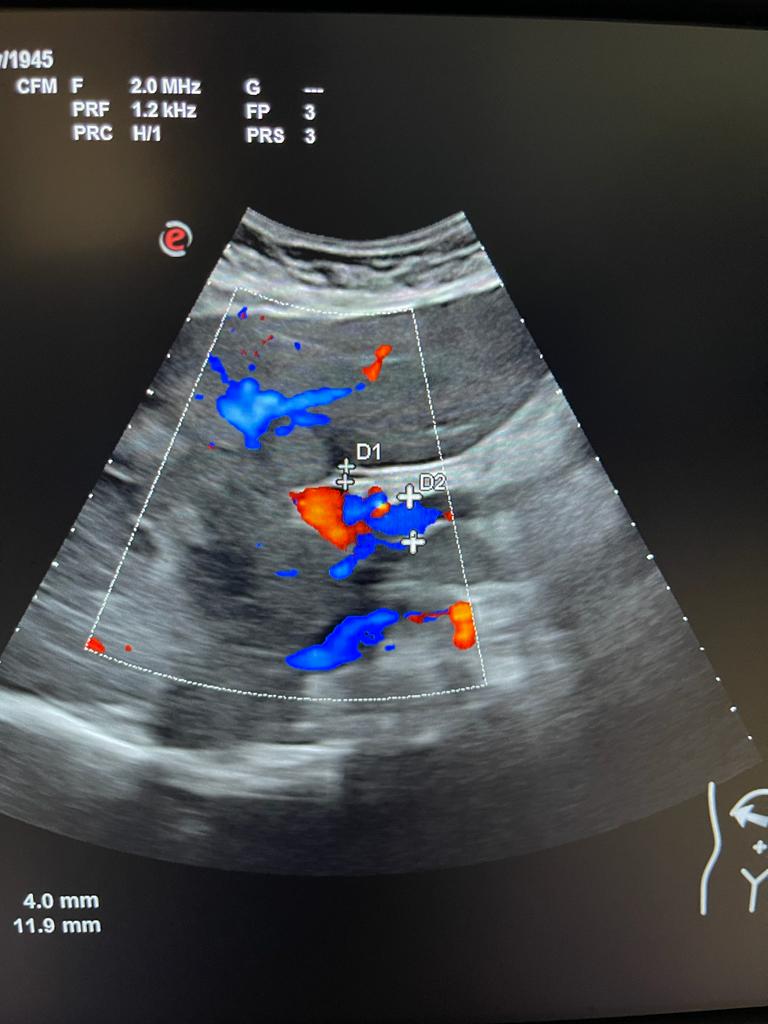

Se aprecia hígado heterogéneo con múltiples LOES hepáticas hiperecogénicas (una de ellas de unos 7x7 cm), sin captación de doppler. Al menos otras 2 LOES de menor tamaño presentan halo hipoecoico. Vesícula replecionada de contornos lisos y sin litiasis en su interior. Ambos riñones visualizados de tamaño normal y sin datos de hidronefrosis.